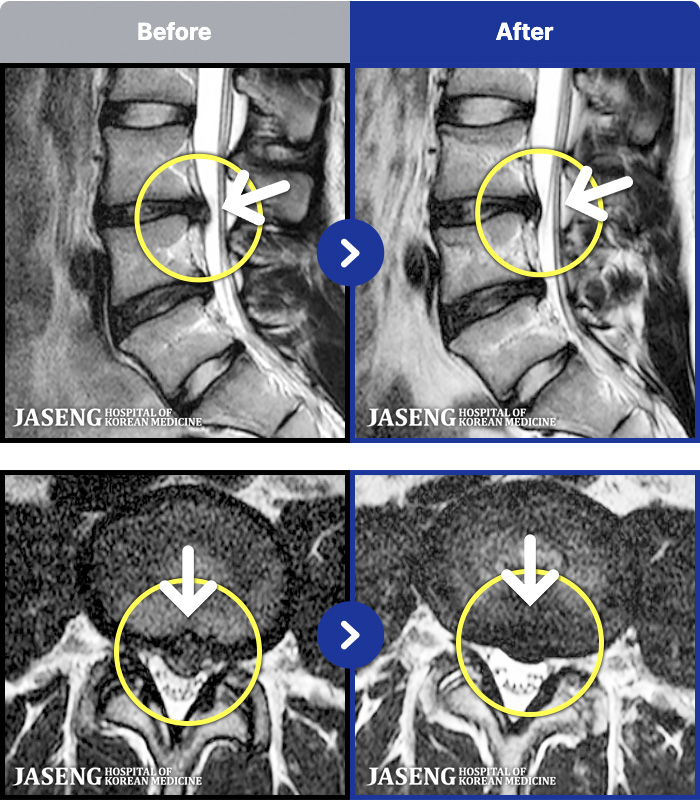

MRI ġ

MRI ũ ʸ Ȯϼ.